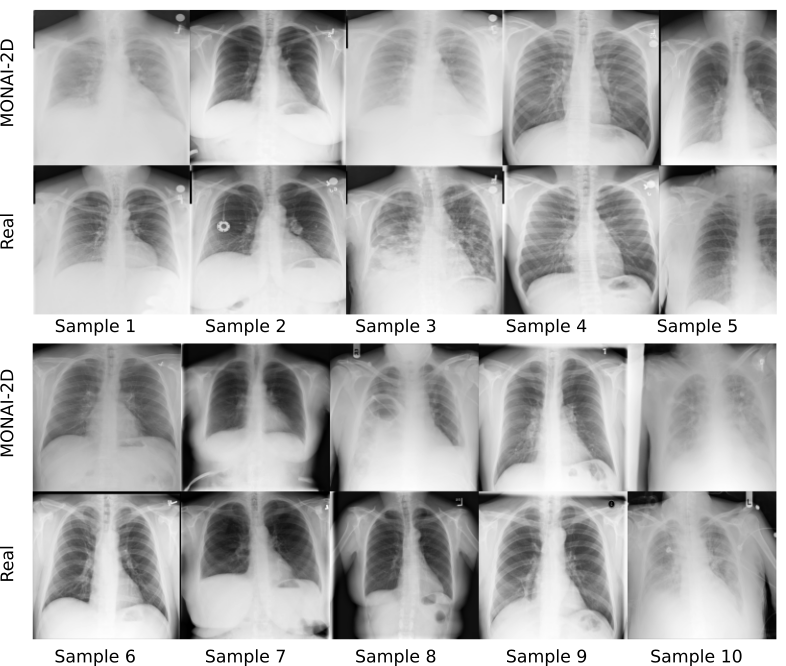

Refer to caption

Figure 7: Representative cross sections of real (Real) and copies (MONAI-2D) detected in the X-ray dataset. Copy candidates show a high resemblance to the corresponding real samples. The network tends to copy even the exact position of the image in case of partial field-of-view coverage.

In the 2D X-ray dataset, 32.6 % of the training data were memorized and 54.5% of the synthetic samples were patient data copies in MONAI-2D. Fig. 7 shows copies alongside the closest training samples. Synthetic samples show a very close resemblance to the training samples. Overall, we observed a high level of patient data was memorized in both 2D and 3D models. Moreover, a very large percentage of synthesized samples were patient data copies, especially in 3D models.

2.2.2 Memorization in Other Generative Models